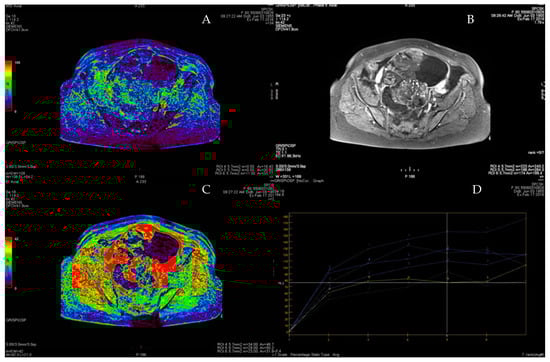

3.4. ROC Curve for LGSC vs. MOC